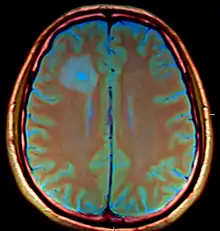

Brain abscess

Brain abscess in a person with a CSF shunt. The abscess is the darker gray region in the lower left of the image (corresponding to the right parietal lobe). The lateral ventricles are visible in black in the center of the brain, adjacent to the abscess.[1]